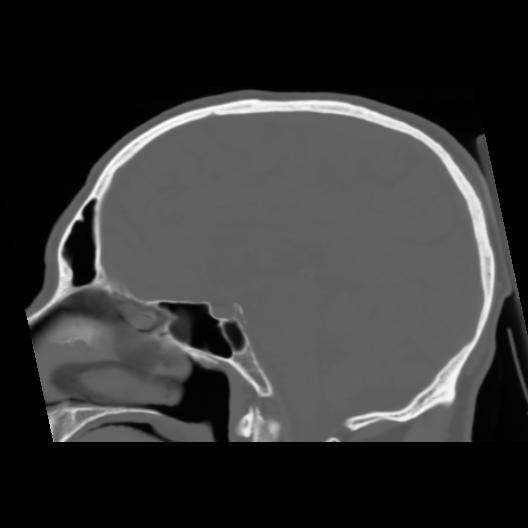

6 CEREBRO,,Sagittal,3.000,CEREBRO,Sagittal,